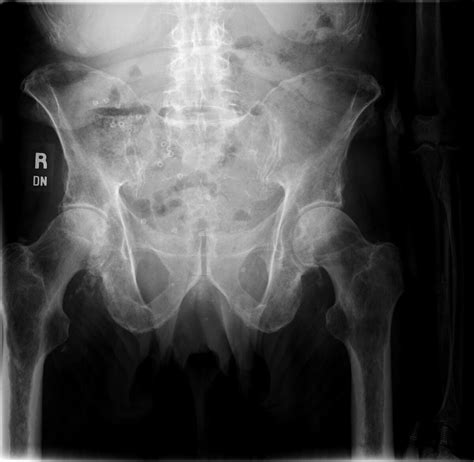

At its core, a lytic lesion is a focal area within the bone structure where mineral density has been significantly reduced. This reduction creates "holes" or voids in the bone, which are easily identified on X-rays as darker, radiolucent patches. The process is usually driven by the activation of osteoclasts—the cells responsible for breaking down bone tissue. When pathological processes, such as the invasion of metastatic cancer cells or inflammatory cytokines, trigger these cells, they erode the bone matrix prematurely.

To determine the etiology of Lytic Skeletal Lesions, radiologists and physicians utilize various imaging modalities, including plain radiographs, computed tomography (CT), magnetic resonance imaging (MRI), and positron emission tomography (PET) scans. Each modality offers different insights into the borders, matrix, and surrounding soft tissue involvement of the lesion.

Effective management of Lytic Skeletal Lesions relies on a systematic imaging protocol. A plain radiograph is almost always the initial step. If the lesion has a sclerotic rim, it may suggest a slow-growing, benign process. Conversely, an ill-defined or "moth-eaten" appearance usually mandates immediate follow-up with more sophisticated imaging like an MRI to assess the extent of the marrow infiltration and soft tissue involvement.